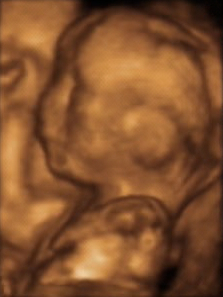

A 3D ultrasound of a human fetus aged 20 weeks

3D ultrasound is a medical ultrasound technique, often used in fetal, cardiac, trans-rectal and intra-vascular applications. 3D ultrasound refers specifically to the volume rendering of ultrasound data. When involving a series of 3D volumes collected over time, it can also be referred to as 4D ultrasound (three spatial dimensions plus one time dimension) or real-time 3D ultrasound.[1]

3D ultrasound is useful, among other things, for facilitating the characterization of some congenital defects, such as skeletal anomalies and heart issues. With real-time 3D ultrasound, the fetal heart rate can be examined in real-time.[4][5]